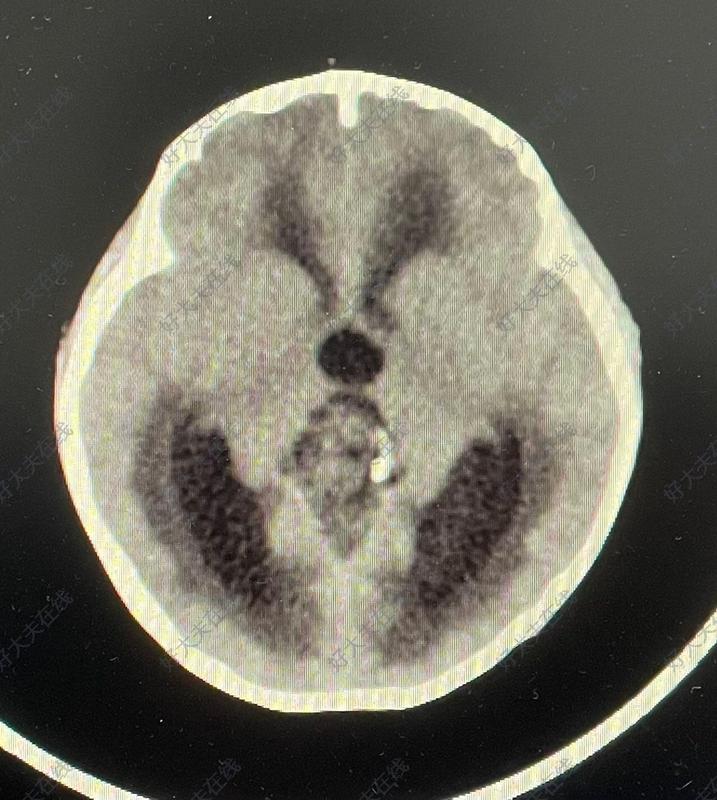

翻譯自MathieuD,Iorio-MorinC.StereotacticRadiosurgeryforPinealRegionTumors.ProgNeurolSurg.2019;34:173-183.doi:10.1159/000493062.作者單位加拿大DivisionofNeurosurgery,DepartmentofSurgery,UniversitédeSherbrooke摘要:松果體區(qū)腫瘤是一組不同組織學實體的異質(zhì)性腫瘤,由于其關鍵部位和頻繁的侵襲行為,治療可能是一個重大挑戰(zhàn)。傳統(tǒng)的治療包括手術切除、分次放療和化療。立體定向放射外科(SRS)正越來越多地用于這些腫瘤的治療。它被用作松果體區(qū)的松果體細胞瘤和乳頭狀腫瘤的主要治療方法,與松果體母細胞瘤和生殖細胞腫瘤的放療或化療相結合,或在腫瘤復發(fā)的情況下作為輔助放療增強劑。報告的發(fā)病率很低,在大多數(shù)情況下包括短暫的動眼神經(jīng)障礙。作為顯微外科切除術的一種非侵入性替代方法,在討論這些具有挑戰(zhàn)性的病例時,應始終考慮SRS。松果體實質(zhì)腫瘤(PPT)PPT起源于松果體細胞,松果體細胞是松果體分泌褪黑素的特殊細胞。世衛(wèi)組織將這些腫瘤分為3個亞型,包括松果體細胞瘤(WHOI級)、中分化PPT(PPTID;WHOII、III級)和松果體母細胞瘤(WHOIV級)。正如預期的那樣,治療和預后高度依賴于腫瘤分級。松果體細胞瘤更常見于年輕至中年成年人。它們是良性病變,完全手術切除可能治愈。然而,對于關鍵部位的其他良性腫瘤,手術與發(fā)病風險顯著相關。越來越多的文獻支持使用SRS作為切除術的微創(chuàng)替代方案。IGKRF系列報告了26名患者,包括24名作為初始治療一部分的SRS患者和2名復發(fā)患者[2]。20年時,累計局部控制率為81%,生存率為76%。Wilson等人[7]對5例次全切除的松果體細胞瘤患者使用SRS(3例為輔助治療手段,2例為腫瘤進展)。平均隨訪65個月后,所有患者均顯示局部腫瘤控制,無并發(fā)癥。Mori等人[3]共治療了6例松果體細胞瘤患者中的13個腫瘤,5年后的PFS為80%。Reyns等人[8]報告了他們對8例松果體細胞瘤患者進行SRS治療的經(jīng)驗。6名患者最初僅接受SRS治療,2名患者接受SRS治療部分切除后的殘余疾病。平均隨訪32個月后,所有患者均存活,腫瘤消退或穩(wěn)定。在他們的文章中,Lekovic等人[6]報道了8例松果體細胞瘤患者的SRS結果。所有腫瘤均在最后一次影像學隨訪中得到控制,隨訪時間為2至56個月。1名患者在SRS后2個月死于無相關原因的腫瘤,該腫瘤在影像學上表現(xiàn)出嚴重退化。圖1描述了一例由原發(fā)性SRS治療的典型松細胞瘤。圖1。一名38歲女性患者因松果體區(qū)腫瘤繼發(fā)于腦積水,表現(xiàn)為復視。她接受了內(nèi)鏡下第三腦室造瘺術和腫瘤活檢。病理證實為松果體細胞瘤。然后,她讓SRS擔任主要治療手段。SRS術后3個月,由于短暫的腫瘤擴張,她的復視暫時惡化。在SRS后的最后36個月隨訪中,腫瘤逐漸消退,臨床上保持穩(wěn)定。PPTID在2007年修訂的WHOCNS腫瘤分類中得到正式認可。它們具有與復發(fā)風險增加相關的組織學特征,通常通過手術切除進行治療。增加分級放射治療或SRS仍然是一個有爭議的問題。在IGKRF系列中,有4名患者在治療前、3名患者在復發(fā)接受SRS治療[2]。SRS后5年的累計局部控制率和生存率分別為50%和56%。在所有其他研究中,分析沒有組織學分層,PPTID的結果與松果體細胞瘤的結果合并在一起,使得比較困難。Park等人[9]報告了9名1級和2級PPT患者的SRS作為主要治療方法。平均隨訪79個月后,所有患者均存活,所有腫瘤均顯示完全或部分緩解。只有1名2級腫瘤患者最終接受了腦脊液播散。Balossier等人[10]還報告了9例1級或2級松果體細胞瘤患者,作為初始治療的一部分,他們單獨或在部分切除后接受SRS治療。所有8名接受影像學隨訪的患者均實現(xiàn)了腫瘤控制,隨訪時間從5個月到76個月不等。Yianni等人[5]報告了11例PPT患者的SRS治療結果(包括6例松果體細胞瘤、3例PPTID和2例松果體母細胞瘤)。他們報告SRS后1年PFS為81%,5年PFS為54%。不幸的是,沒有按照腫瘤分級進行分析,這使得解釋更加困難。據(jù)推測,通過包括松果體細胞瘤,這些研究高估了SRS對PPTID的療效。松果體母細胞瘤是一種高度惡性的腫瘤,通常發(fā)生在兒童和年輕人身上。建議的治療包括最大限度的手術切除,然后分次放療和化療。據(jù)報道,SRS主要出現(xiàn)在復發(fā)的情況下,或作為初級治療后的局部增強治療。IGKRF系列包括13名患者,其中8名患者SRS作為一種加強治療方式,在5例復發(fā)時使用SRS。局部控制和生存率較差,5年累計率分別為27%和48%。作為多模式管理的一部分,Mori等人[3]對2例松母細胞瘤患者的4個腫瘤進行了SRS。2名患者分別在SRS后3個月和13個月出現(xiàn)腫瘤進展。在Reyns等人[8]的研究中,5例松果體細胞瘤患者在手術切除、分割放療和化療的基礎上,還接受了SRS治療。2例患者的病情仍得到控制,2例患者出現(xiàn)局部腫瘤進展延遲,1例局部腫瘤控制患者出現(xiàn)遠處腦播散。2名患者死于腫瘤進展。在他們的系列研究中,Lekovic等人[6]治療了1例復發(fā)性松果體母細胞瘤患者。45個月后,患者仍然活著,在影像學上有一個穩(wěn)定的腫瘤。圖2描述了一名患者的情況,作為多模式初始管理的一部分,她接受了SRS治療。圖2。一名21歲女性患者出現(xiàn)腦積水導致顱內(nèi)高壓綜合征。她接受了內(nèi)鏡下第三腦室造瘺術和腫瘤活檢。病理結果為松果體母細胞瘤。她接受了伽瑪?shù)斗派渫饪浦委?,隨后接受了分次放射治療和化療。診斷90個月后,她仍無疾病,神經(jīng)功能正常。松果體區(qū)乳頭狀腫瘤2007年修訂版將松果體區(qū)乳頭狀腫瘤(PTPR)納入WHOCNS腫瘤分類。它們被認為是由亞鰓器官的特殊室管膜細胞產(chǎn)生的。它們可以被歸類為WHOII級或III級腫瘤,但這兩級腫瘤即使在大體全切除后也有很高的局部復發(fā)傾向。最優(yōu)管理仍然是一個有爭議的問題。前期放射治療或化療尚未證明能降低復發(fā)風險[11]。鑒于局部復發(fā)的高風險,許多作者正在研究SRS的作用。IGKRF研究包括6名PTPR患者[2]。5名患者在組織學診斷后接受SRS作為初始治療的一部分,另1名患者在大體全切除后復發(fā)接受治療。5名患者出現(xiàn)局部復發(fā),導致5年時的累計局部控制率僅為33%。所有這些患者對復發(fā)的腫瘤重復SRS,導致4名患者的局部控制時間延長。5年時的累計生存率為100%。Yianni等人[5]的系列研究包括2名PTPR患者。無法進行長期隨訪,但在SRS后1年,2名患者均顯示腫瘤控制。Balossier等人[10]報告了1例部分切除后出現(xiàn)SRS的患者,術后6個月腫瘤穩(wěn)定。Fauchon等人[11]發(fā)表了文獻中最大的PTPR回顧性隊列,共包括43名患者。只有2名患者在活檢和部分切除后接受了SRS檢查。2名患者在未指定的時間間隔后均出現(xiàn)腫瘤復發(fā),1名患者最終死亡。Shakir等人[12]報告了1例PTPR患者,在部分切除和替莫唑胺化療1年后,補充SRS。腫瘤逐漸消退,9年后仍處于控制狀態(tài)。Riis等人[13]報告的另1名患者在立體定向活檢后出現(xiàn)SRS,并在5年后證明腫瘤持續(xù)消退。Cardenas等人[14]發(fā)表了1例SRS后腫瘤控制7年的患者。當時,他有腫瘤進展,接受了大體全切除術,沒有復發(fā)。圖3顯示了一名年輕患者的情況,該患者作為治療的一部分接受了2次SRS治療她的PTPR。圖3。一名4歲女性患者因松果體區(qū)腫瘤繼發(fā)腦積水。她接受了部分腫瘤切除術,證實了PTPR的診斷。然后她接受SRS作為殘余腫瘤的輔助治療。在接下來的幾個月里,腫瘤立即消退。SRS術后18個月,MRI顯示無癥狀局部腫瘤復發(fā)。她對復發(fā)的腫瘤進行了重復SRS治療,隨后出現(xiàn)完全的腫瘤反應,在最后一次手術后的88個月的最新隨訪中仍持續(xù)穩(wěn)定。其他腫瘤松果體區(qū)可出現(xiàn)腦膜瘤、膠質(zhì)瘤和轉(zhuǎn)移瘤。由于它們的影像學特征,診斷這些病變通常很簡單。SRS通常用于其他部位的腫瘤治療,具有可預測且眾所周知的反應特征。SRS治療這些腫瘤的主要考慮因素是限制對鄰近腦干的劑量,以降低輻射誘發(fā)毒性的風險。討論關于SRS在松果體區(qū)腫瘤中的應用的文獻仍然有限,并且很難從現(xiàn)有發(fā)表的研究中得出有意義的結論。其中一個主要原因是,為了補償有限的患者數(shù)量,作者必須將不同的腫瘤組織學亞組匯總在一起,從而得出可能不適用于所有特定腫瘤的局部控制和生存數(shù)據(jù)[3,5,6,15]。IGKRF最近發(fā)表的研究試圖通過組織學分層分析來緩解這一事實,從而提供更好的質(zhì)量數(shù)據(jù)來指導患者管理[2]。然而,現(xiàn)有的文獻已經(jīng)證明,SRS對于某些松果體區(qū)患者是一種有用的治療方式腫瘤。對于生殖細胞瘤,SRS的主要興趣在于它能夠為腫瘤床提供適形放射增強,從而允許使用低劑量的分次放射治療,或在復發(fā)時使用。在非生殖細胞瘤的生殖細胞腫瘤(NGGCT)的情況下,SRS可作為局部增強劑,用于切除術后殘余腫瘤,結合分次放療和化療,或在復發(fā)的情況下。這似乎也是松果體母細胞瘤患者的主要適應癥。在大多數(shù)已發(fā)表的研究中,對于松果體細胞瘤,SRS似乎可以誘導長期的腫瘤生長控制。因此,將預先SRS作為腫瘤切除的替代方案作為主要管理方式似乎是合理的。這可能也適用于PPTID,盡管在許多研究中,由于其與WHOI級腫瘤的分組,這些病變的文獻很難分析??梢钥紤]增加分級放射治療,尤其是在III級腫瘤中。最后,對于PTPR患者,SRS似乎是一種合理的主要治療選擇,因為即使是患有各種組織學腫瘤的患者,SRS也有局部復發(fā)的趨勢。圖4給出了一個建議的SRS整合算法,用于松果體區(qū)腫瘤的治療。圖4。針對組織學證實為松果體區(qū)腫瘤的患者提出的管理流程。在大多數(shù)研究中,與SRS相關的并發(fā)癥是合理的,與手術切除相比是有利的。在IGKRF研究中,28%的病例出現(xiàn)了影像學上輻射引起的變化[2]。15%的患者出現(xiàn)臨床惡化,其中9%出現(xiàn)新的局灶性缺損,7%出現(xiàn)新的Parinaud?綜合征,3%出現(xiàn)腦積水。Park等人[9]報告,接受SRS治療的9名PPT患者中有1名出現(xiàn)暫時性記憶障礙。Yianni等人[5]在他們的44名不同組織學腫瘤患者隊列中,只有一例SRS后出現(xiàn)短暫性復視。在使用SRS治療的13例PPT中,Reyns等人[8]報告了3名患者出現(xiàn)了新的暫時性復視,只有1名患者出現(xiàn)了新的永久性復視。Amendola等人[15]報告,在20名患有各種松果體腫瘤的患者隊列中,沒有SRS相關的并發(fā)癥。在另一組17例不同組織學診斷的患者中,未發(fā)現(xiàn)與SRS手術相關的并發(fā)癥[6]。由于事件數(shù)量和接受治療的患者總數(shù)較少,沒有變量與發(fā)病風險增加相關。在大多數(shù)研究中,腫瘤的邊緣劑量在10-20Gy之間變化。根據(jù)有限的可用文獻,無法提出正式的劑量建議。由于SRS通常用于輔助治療或之前的分次放療后,因此建議相應地調(diào)整劑量,并將腦干的劑量保持在可耐受的范圍內(nèi)似乎是合理的。如前所述,松果體區(qū)腫瘤的治療,包括SRS的使用,應根據(jù)具體的組織學診斷進行調(diào)整。因此,只要可行,應盡一切努力獲取腫瘤組織。然而,這可能并非在所有情況下都可行,因為患者共病、拒絕手術或手術后可用組織有限。IGKRF研究包括10名僅基于影像學診斷的SRS患者,無組織學證實[2]。累計局部控制率和5年生存率分別為61%和67%,與整個系列的匯總結果相似。Li等人[16]報道了一個大系列,包括147名僅基于影像學和臨床診斷的松果體病變SRS患者。他們報告了69%的病例出現(xiàn)了最初的腫瘤消退,在SRS術后1年、3年和5年仍然存活的患者中,局部控制率分別為97%、94%和91%。1年、3年和5年的生存率分別為80%、72%和67%。這些結果似乎支持在選定的患者中使用SRS,即使沒有病理證實。在這些情況下,管理應基于基于所有其他特定患者信息的最有可能的診斷,如果認為必要,應提供適當?shù)妮o助治療(在這種情況下,建議的管理流程見圖5)圖5。針對組織學未知的松果體區(qū)腫瘤患者提出的管理流程結論鑒于松果體區(qū)腫瘤的罕見性,可用于指導治療的證據(jù)水平較低。在現(xiàn)有研究的范圍內(nèi),SRS似乎是一種安全的方式,其有效性和作用取決于組織學。對于松果體細胞瘤和PTPR的主要治療,SRS可以作為手術的合理替代方案,后者更容易復發(fā)。對于生殖細胞腫瘤和松果體母細胞瘤,SRS可以在復發(fā)時使用,也可以作為多模式初級治療的一部分,作為一種輔助手段,減少分次放射治療的劑量。作為顯微外科切除術的一種非侵入性替代方法,在討論這些具有挑戰(zhàn)性的病例時,應始終考慮SRS。(圖:山東大學第二醫(yī)院神經(jīng)外科配置的?LeksellGammaKnifePerfexion)